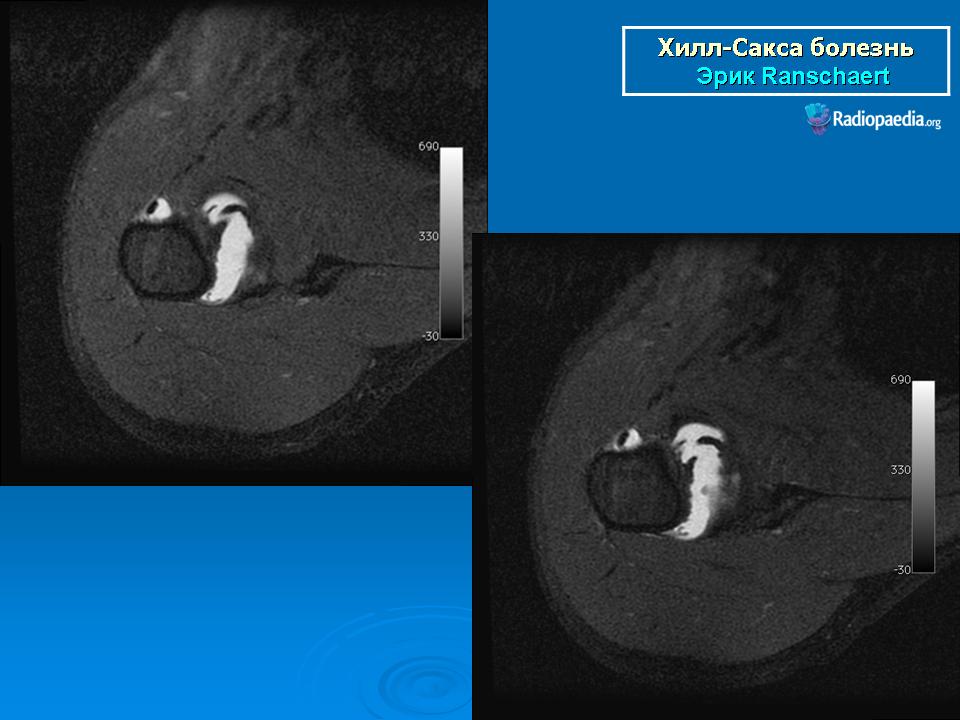

На рентгенограмме плечевого сустава определяется умеренный остеопороз головки плечевой кости. Иногда на ее задненаружной поверхности позади вершины большого бугорка выявляется вдавленный дефект (повреждение Хилл-Сакса). Дефект четко виден на рентгенограмме в аксиальной проекции. Аналогичный, но менее выраженный дефект может быть выявлен в зоне передненаружного края суставной впадины лопатки. Также в диагностике причин привычного вывиха плеча помогает МРТ исследование.